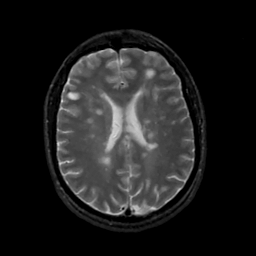

MR Study #12, May 12, 1991 -- Slice #31